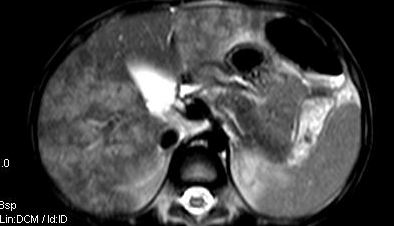

标题: V0176(MRI):小儿发热,肝脾大,肝内病变 [打印本页]

标题: V0176(MRI):小儿发热,肝脾大,肝内病变

5岁,2006年8月曾行阑尾炎手术,现发热半年